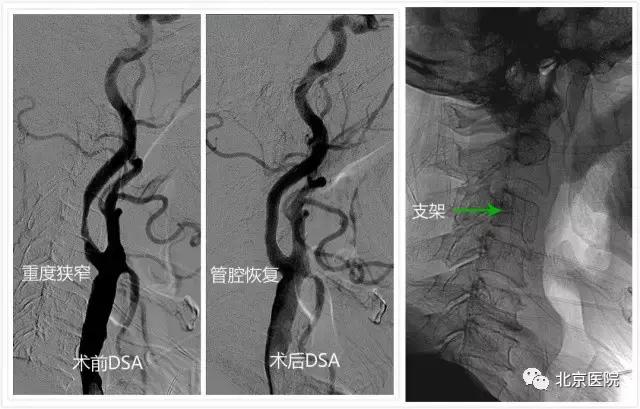

日前,一位88岁老人家属发来的短信让北京医院神经外科的全体医护人员倍感欣喜。原来,这位老人在春节前因“突发左侧肢体瘫痪”在我院确诊为“急性脑梗死”和“颈动脉重度狭窄”,家人告诉医生,老人几年前就因“记性不好、整天瞌睡”在其他医院诊断了“老年痴呆”,现在已“生活自理困难”。在完善相关准备后,我院神经外科为其实施了“微创”的颈动脉狭窄支架成形术。术后老人一改之前的“萎靡不振”,竟然“兴致勃勃”地与旁人聊起了家常,第二天就要求出院回家过春节去……这不,春暖花开,老人特意嘱托家属发来短信,感谢北京医院神经外科医护人员帮他度过了一个健康快乐的春节。

针对颈动脉狭窄,早在上世纪90年代,北京医院神经外科刘树山主任就开展了颈动脉内膜剥脱术;2002年,在国内最早报道了采用脑保护装置辅助进行颈动脉狭窄支架成形术。神经外科还与神经内科、放射科、超声医学科、核医学科等兄弟科室开展长期合作,围绕颈动脉狭窄患者的认知功能、脑血流灌注、颈动脉斑块稳定性等热点和难点问题,进行了深入的临床和基础研究;先后承担了原国家卫生部临床学科重点项目、首发基金项目、北京医院“121项目”等多项科研课题;发表相关学术论文30余篇;主办了大型脑血管病研讨会10余次。值得一提的是,作为国家老年医学中心,北京医院接诊的颈动脉狭窄患者一直以老年、高龄患者居多,仅在2016年,就治疗了老年颈动脉狭窄患者74例(占总数70%多),无一例出现严重手术并发症。